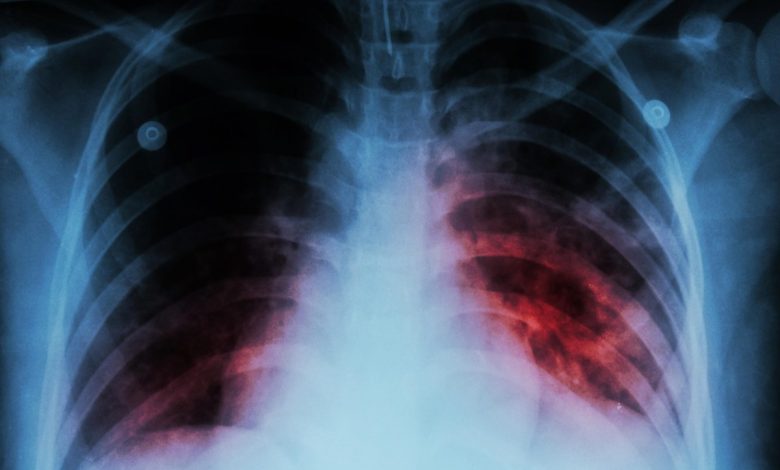

La tuberculosis volvió a instalarse en la agenda sanitaria tras los datos difundidos por el Ministerio de Salud y Deportes, y en Mendoza las cifras muestran un escenario particular: si bien hay casos activos, la provincia mantiene una tasa significativamente más baja que el promedio nacional.

Según confirmó Beatriz Ocaña, jefa del Programa de Tuberculosis, durante 2025 se notificaron 122 casos en el sistema nacional, lo que representa una tasa de 6 casos cada 100.000 habitantes. El dato contrasta con la media del país, que asciende a 37,3 cada 100.000, con mayor incidencia en el Área Metropolitana de Buenos Aires y provincias del norte como Jujuy, Formosa y Chaco.

En términos históricos, las cifras en Mendoza han mostrado cierta estabilidad y una tendencia a la baja. “Veníamos con tasas de 8, en algunos momentos de 9, el año pasado fue de 7 y ahora cerramos en 6”, precisó la funcionaria.

Esto ubica a la provincia en una situación relativamente favorable, aunque lejos de relajar la vigilancia. A nivel país, el incremento sostenido de casos mantiene en alerta a las autoridades sanitarias.